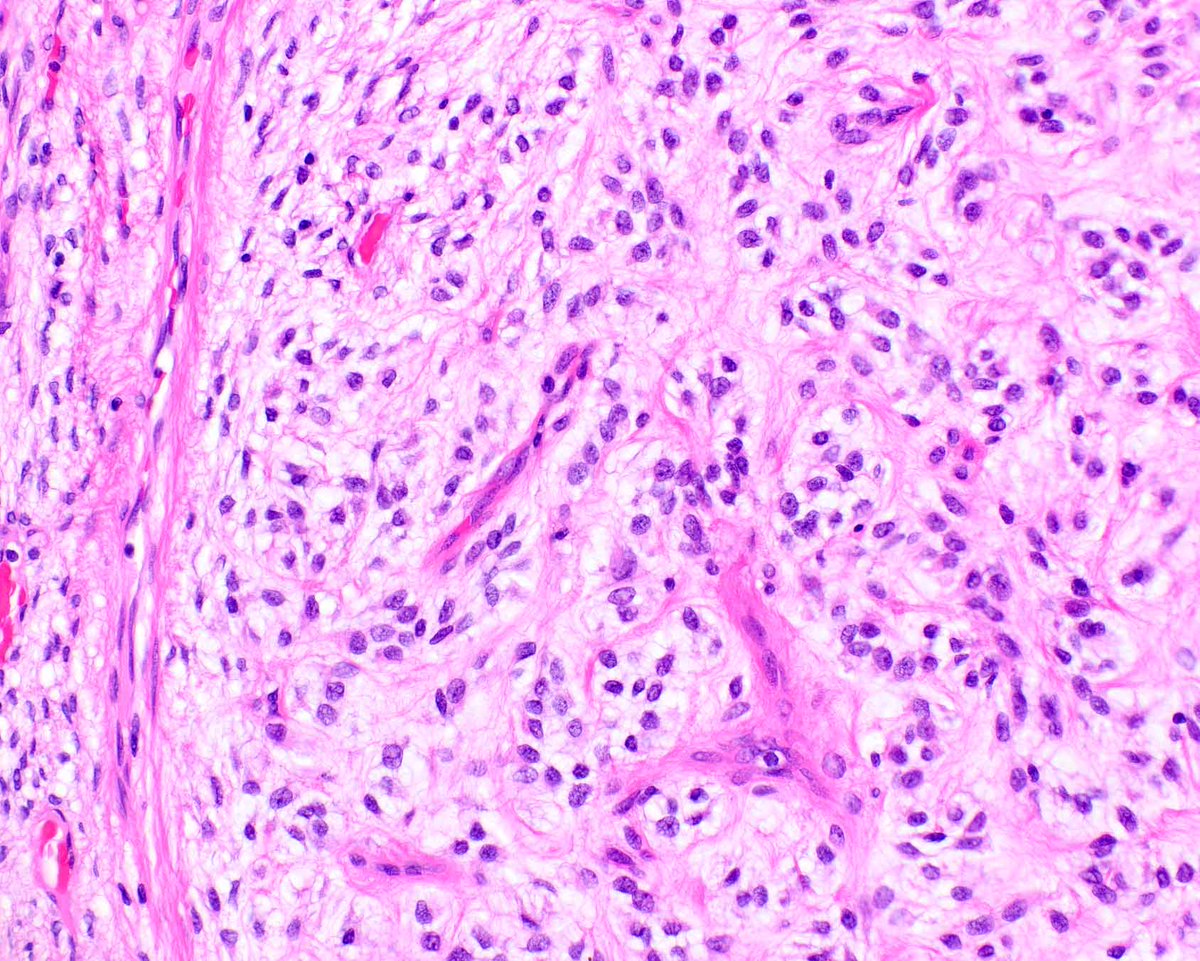

This HPV-associated anal lesion most likely harbors a CYLD mutation based on the morphology. It is essentially a basaloid variant of squamous cell carcinoma that produces peculiar basement membrane material.

Williams EA, Montesion M, Sharaf R, Corines J, Patel PJ, Gillespie BJ, Pavlick DC, Sokol ES, Alexander BM, Williams KJ, Elvin JA, Ross JS, Ramkissoon SH, Hemmerich AC, Tse JY, Mochel MC. CYLD-mutant cylindroma-like basaloid carcinoma of the anus: a genetically and morphologically distinct class of HPV-related anal carcinoma. Mod Pathol. 2020 Dec;33(12):2614-2625. PMID: 32461623; PMCID: PMC7685972.